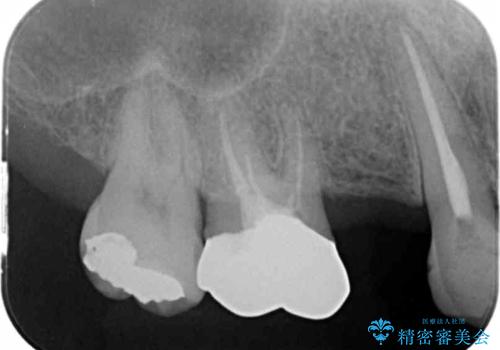

- 銀歯だらけの口腔内で将来歯がなくなるのではないかと不安になり、精査、治療を求めて来院されました。

歯周病や虫歯・強度の問題がありながらも無理やり残していた長期的な予後の見込めない歯を抜去し、インプラントを用いてしっかりと噛めるような口腔内環境の確立を目指します。